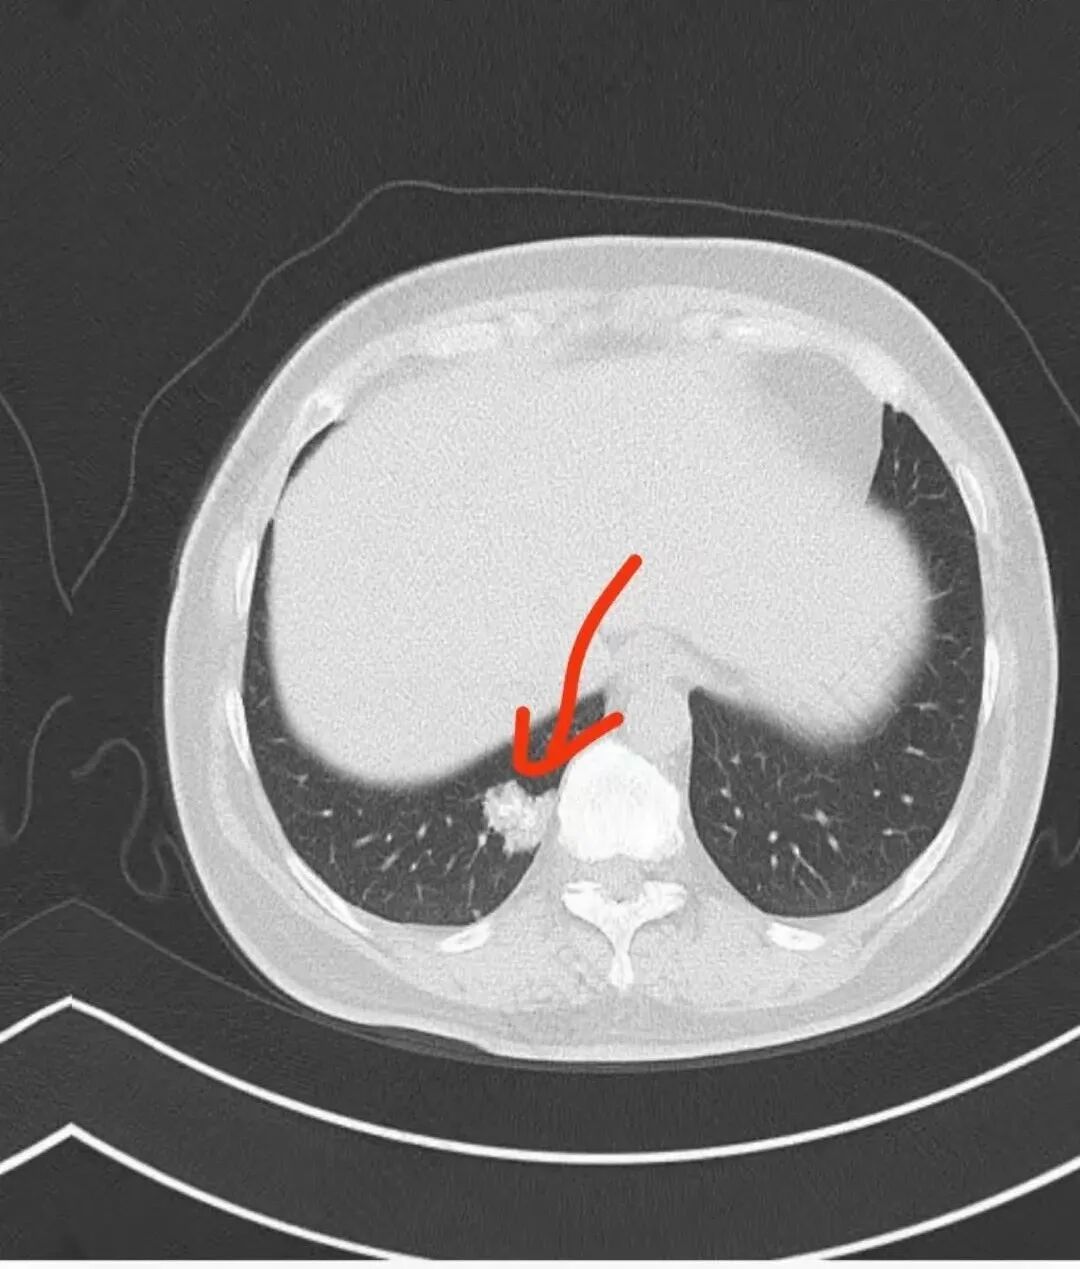

中年女性,右肺下叶后基底段胸膜下不规则稍低密度结节影,内见多发钙化,边缘部分平直,邻近胸膜下脂肪间隙清晰,增强扫描呈均匀轻中度强化,病灶边缘见少许小斑片状影,考虑良性病变,炎性肉芽肿可能,鉴别错构瘤

右肺下叶后基底段结节,形态不规则,有分叶和毛刺,内可见爆米花样钙化,实性成分有强化,绿色无坑肯定考虑错构瘤,晨读估计不会这么简单,所以考虑腺癌?转移性腺癌?鉴别结核

右肺下叶胸膜下不规则结节,分叶,其内爆米花样钙化,轻度强化,考虑错构瘤,鉴别腺癌

中年女性,无临床症状,胸部CT右肺下叶基底段实变影,边缘清楚,部分边缘刀切征,中间大部分钙化,局部胸膜无侵犯,似乎可见支气管充气征,考虑炎性肉芽肿,错构瘤待排

这个形态还是像腺癌,有膨隆有分叶,边缘磨玻璃边界清,非钙化部分轻度强化。腺癌可以钙化的,估计是干扰项

右肺下叶分叶状实性结节伴钙化,胸膜牵拉似有侵犯,增强后轻度强化,倾向恶性,腺癌可能。

右肺结节,边界清楚,中心钙化,钙化边缘模糊,轻度强化,考虑腺癌,鉴别错构瘤。

右肺下叶内基底段胸膜下分叶状肿块,边界清,密度不均匀,有成簇状钙化(与错构瘤钙化不同),实性部分有强化,肿块边缘凹陷明显(有收缩力),周围集血管束特点,方向首选肺肿瘤,考虑肺腺Ca。

肿块出现L征,具有恶性特点: